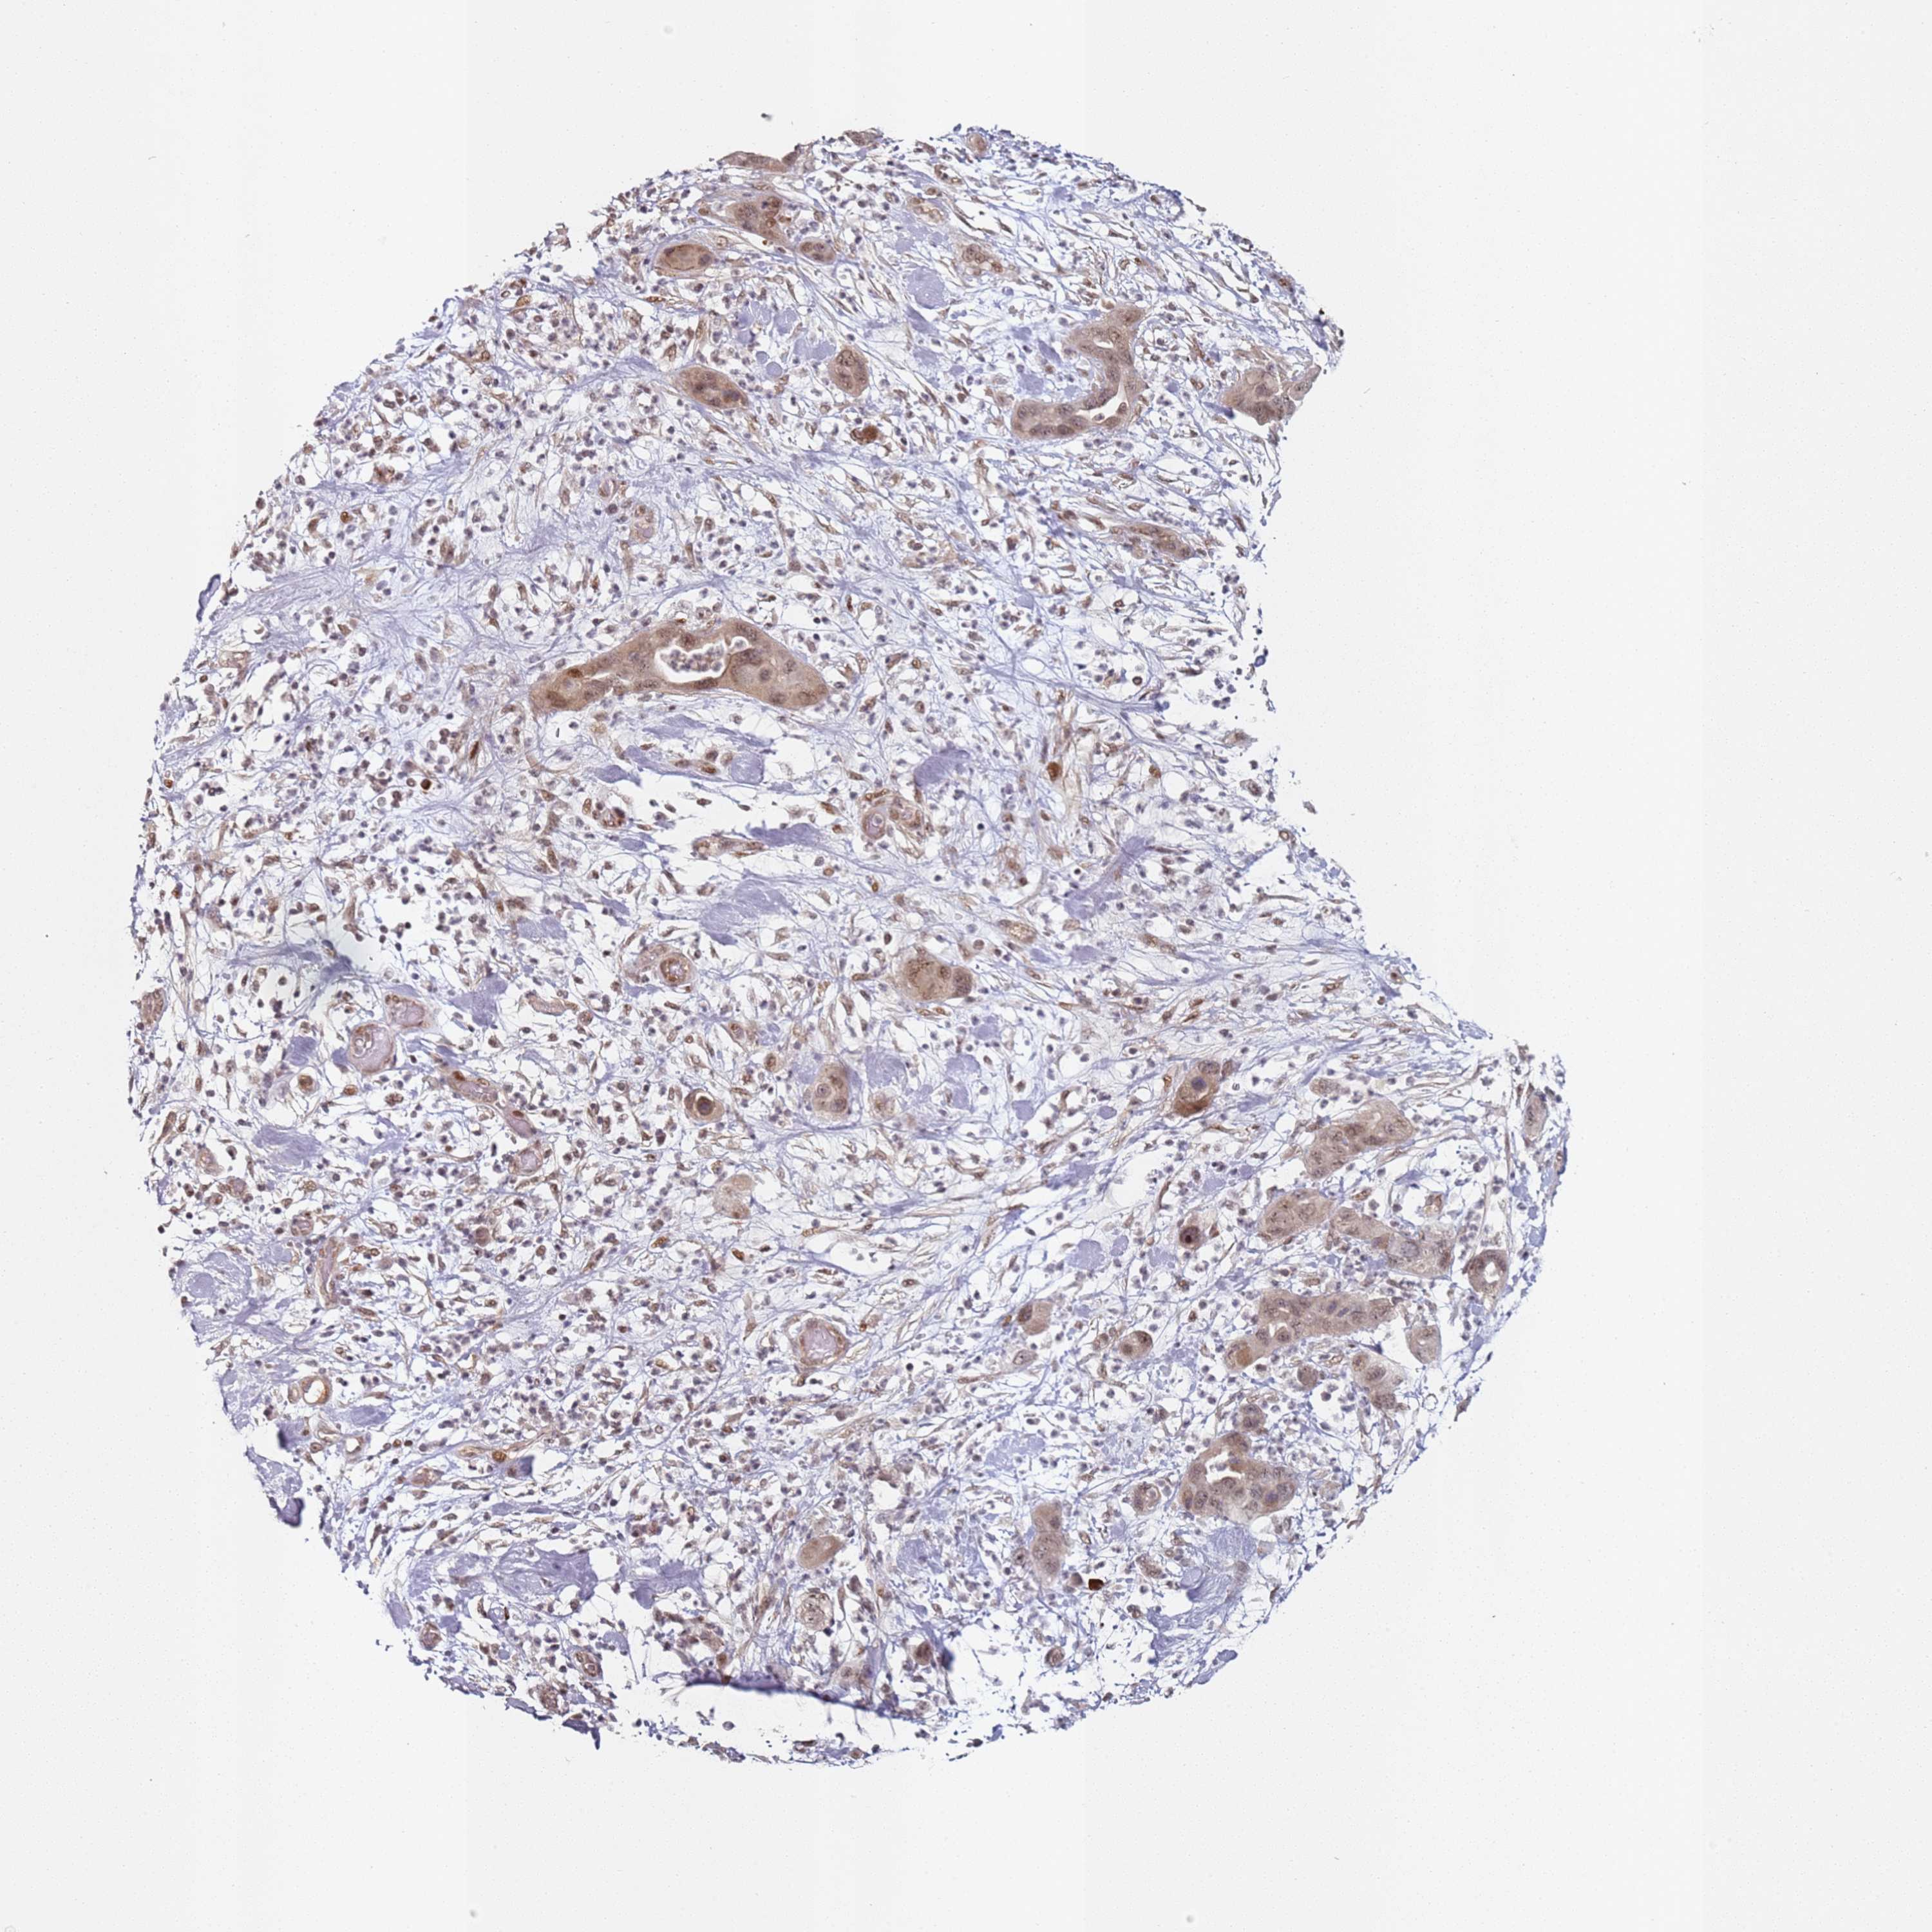

PANCREATIC CANCER - Protein expressioni

A mouse-over function shows sample information and annotation data. Click on an image to view it in a full screen mode. Samples can be filtered based on level of antibody staining by selecting one or several of the following categories: high, medium, low and not detected. The assay and annotation is described here.

Note that samples used for immunohistochemistry by the Human Protein Atlas do not correspond to samples in the TCGA dataset.

Antibody stainingi

Antibody staining in the annotated cell types in the current human tissue is reported as not detected, low, medium, or high, based on conventional immunohistochemistry profiling in selected tissues. This score is based on the combination of the staining intensity and fraction of stained cells.

Each image is clickable and will lead to virtual microscopy that enables deeper exploration of all samples and also displays staining intensity scores, fraction scores and subcellular localization as well as patient and tissue information for each sample.

Antibody HPA046871

Staining

High

Medium

Low

Not detected

Intensity

Strong

Moderate

Weak

Negative

Quantity

>75%

75%-25%

<25%

None

Location

Nuclear

Cytoplasmic/membranous

Cytoplasmic/membranous,nuclear

Adenocarcinoma, NOS